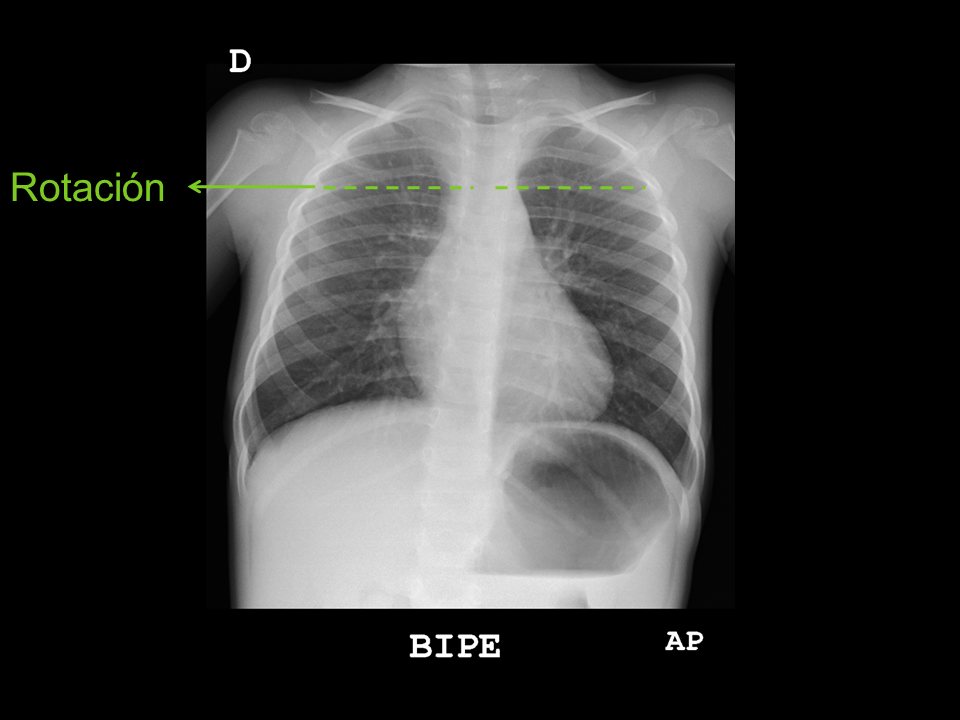

• Posición, rotación: las apófisis espinosas dorsales deben identificarse equidistantes de la pared torácica izquierda y derecha.